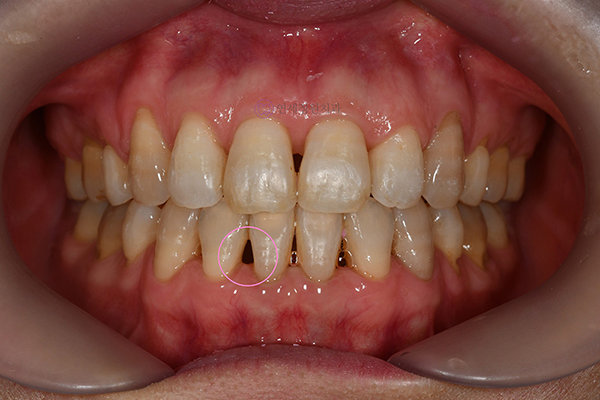

어릴 때 교정을 할 수록 교정 치료시 동반되는 부작용도 최소화시킬 수 있습니다. 어릴 때 교정치료를 받을수록 교정 후 블랙트라이앵글(잇몸뼈가 내려가서 치아 사이에 구멍이 뚫린 것처럼 까맣게 보이는 삼각형 모양의 빈 공간)이 생기는 케이스는 거의 드뭅니다.

교정치과 연세정원치과

그리고, 저는 무엇보다 아이들이 자신감있게 활짝 웃었으면 좋겠습니다. 위 앞니가 튀어나왔다고, 치아가 삐뚤빼뚤하다고 아이들이 본인의 외모에 자신감을 갖지 못하거나, 웃을 때 입을 가리고 웃지 않기를 바랍니다. 초등학생~중학생 시기는 감수성이 예민하고 외모에 관심이 높아지는 시기이기 때문에, 치아 교정으로 가지런한 치아를 가지게 된다면 아이들이 자신감도 회복하고 정서적으로도 안정이 될 수 있을 것입니다.